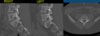

- Compression of vertebral body on CT; wedge-shaped formation on x-ray (see attached images)